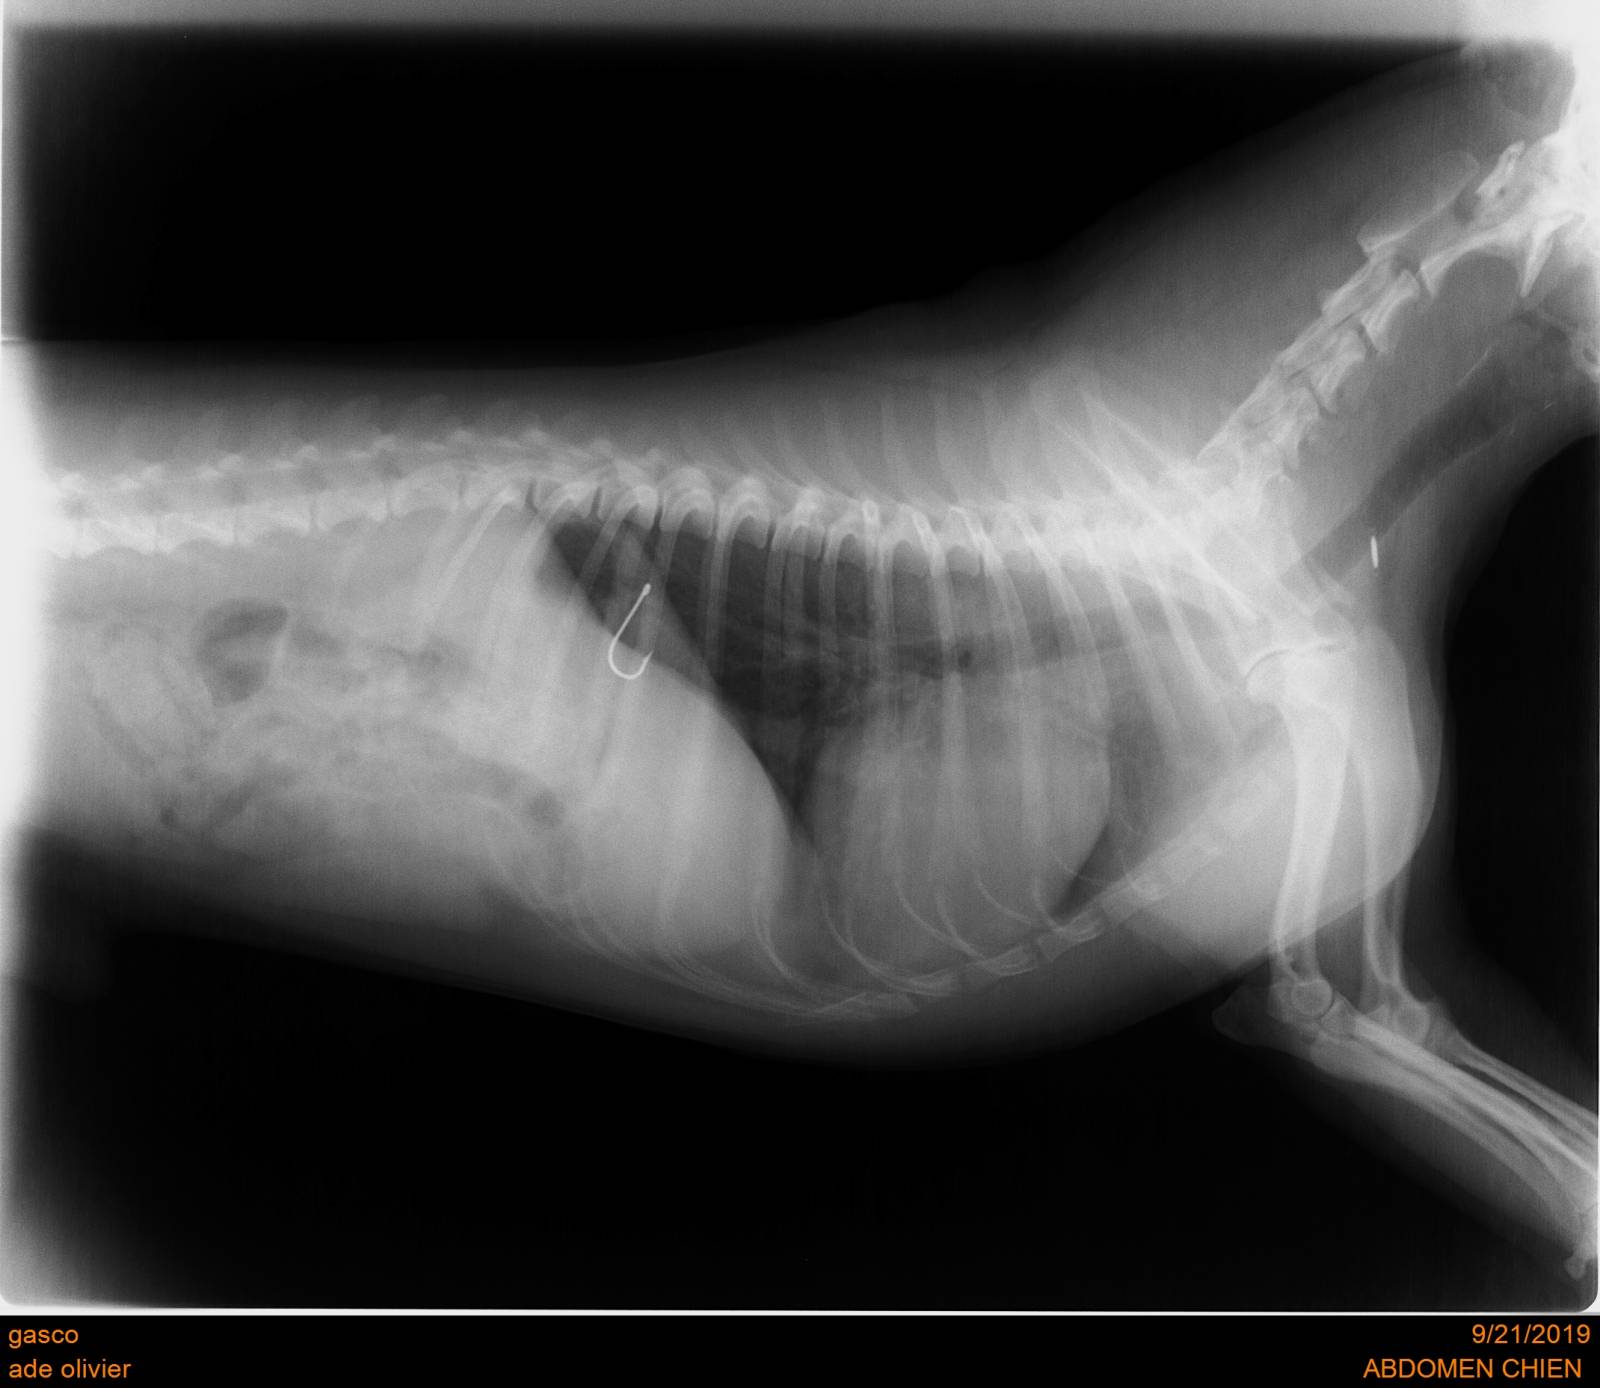

L'ingestion de corps étranger est fréquente chez les carnivores domestiques. Les symptômes peuvent être très variés : vomissements aigues ou chroniques, diarrhée, absence de selles, douleurs abdominales plus ou moins marquées, traces de sang dans les selles, dysorexie ou anorexie totale, amaigrissement rapide. La gravité des lésions intestinales occasionnées par le corps étranger est liée au corps étranger lui même (objets perforants, objets linéaires) et à sa localisation dans le système digestif (occlusion totale ou partielle ?). La visualisation en imagerie peut être difficile et demande souvent la combinaison de radiographies, d'échographies voire de la réalisation d'une succession de radiographies sur plusieurs heures appelée transit baryté (ingestion d'un produit de contraste visible à la radiographie dont on suit l'avancée dans le système digestif).